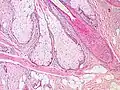

Sebaceous glands are found in hair-covered areas, where they are connected to hair follicles. One or more glands may surround each hair follicle, and the glands themselves are surrounded by arrector pili muscles, forming a pilosebaceous unit. The glands have an acinar structure (like a many-lobed berry), in which multiple glands branch off a central duct. The glands deposit sebum on the hairs and bring it to the skin surface along the hair shaft. The structure, consisting of hair, hair follicles, arrector pili muscles, and sebaceous glands, is an epidermal invagination known as a pilosebaceous unit.[4]